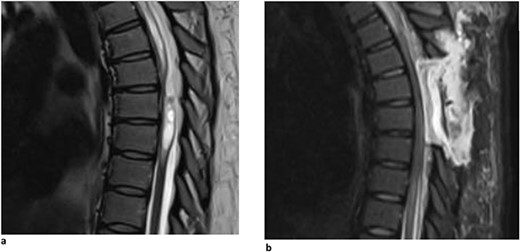

A 40-year-old woman presented with a 3-year history of progressively worsening interscapular pain radiating around the rib cage on the right, difficulty with ambulation, and right foot numbness. Physical examination demonstrated myelopathic symptoms, with 3+ reflexes in both lower extremities, clonus, and Babinski, as well as difficult tandem gait. Thoracic MRI showed an arachnoid web at the T5-T6 vertebral levels (Fig. 2a). The patient underwent a T5-T6 laminectomy with intradural exploration. A large arachnoid web was encountered and resected using microsurgical tools and technique. Postoperatively, the patient reported improvement in her pain and ambulation. Follow-up MR imaging demonstrated resolution of the dorsal indentation and cord expansion (Fig. 2b).

(a) Dorsal indentation demonstrated in thoracic spine preoperatively (Patient B). (b) Postlaminectomy and resection of posterior arachnoid web demonstrating resolution of dorsal indentation and cord signal changes (Patient B).